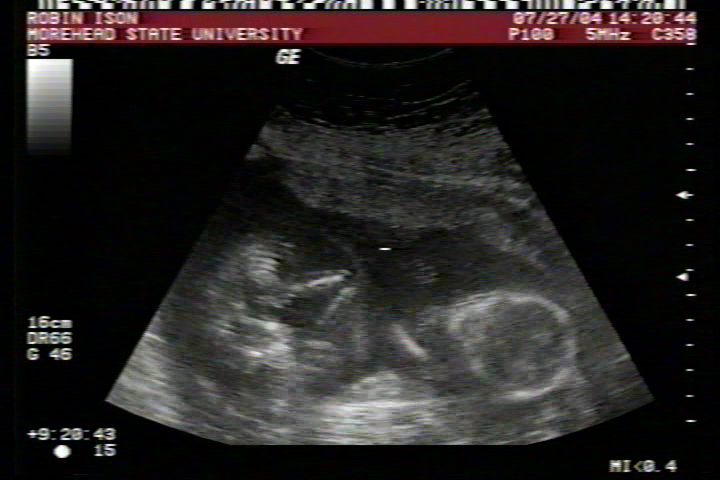

Pictures from Ultrasound at 17 weeks.